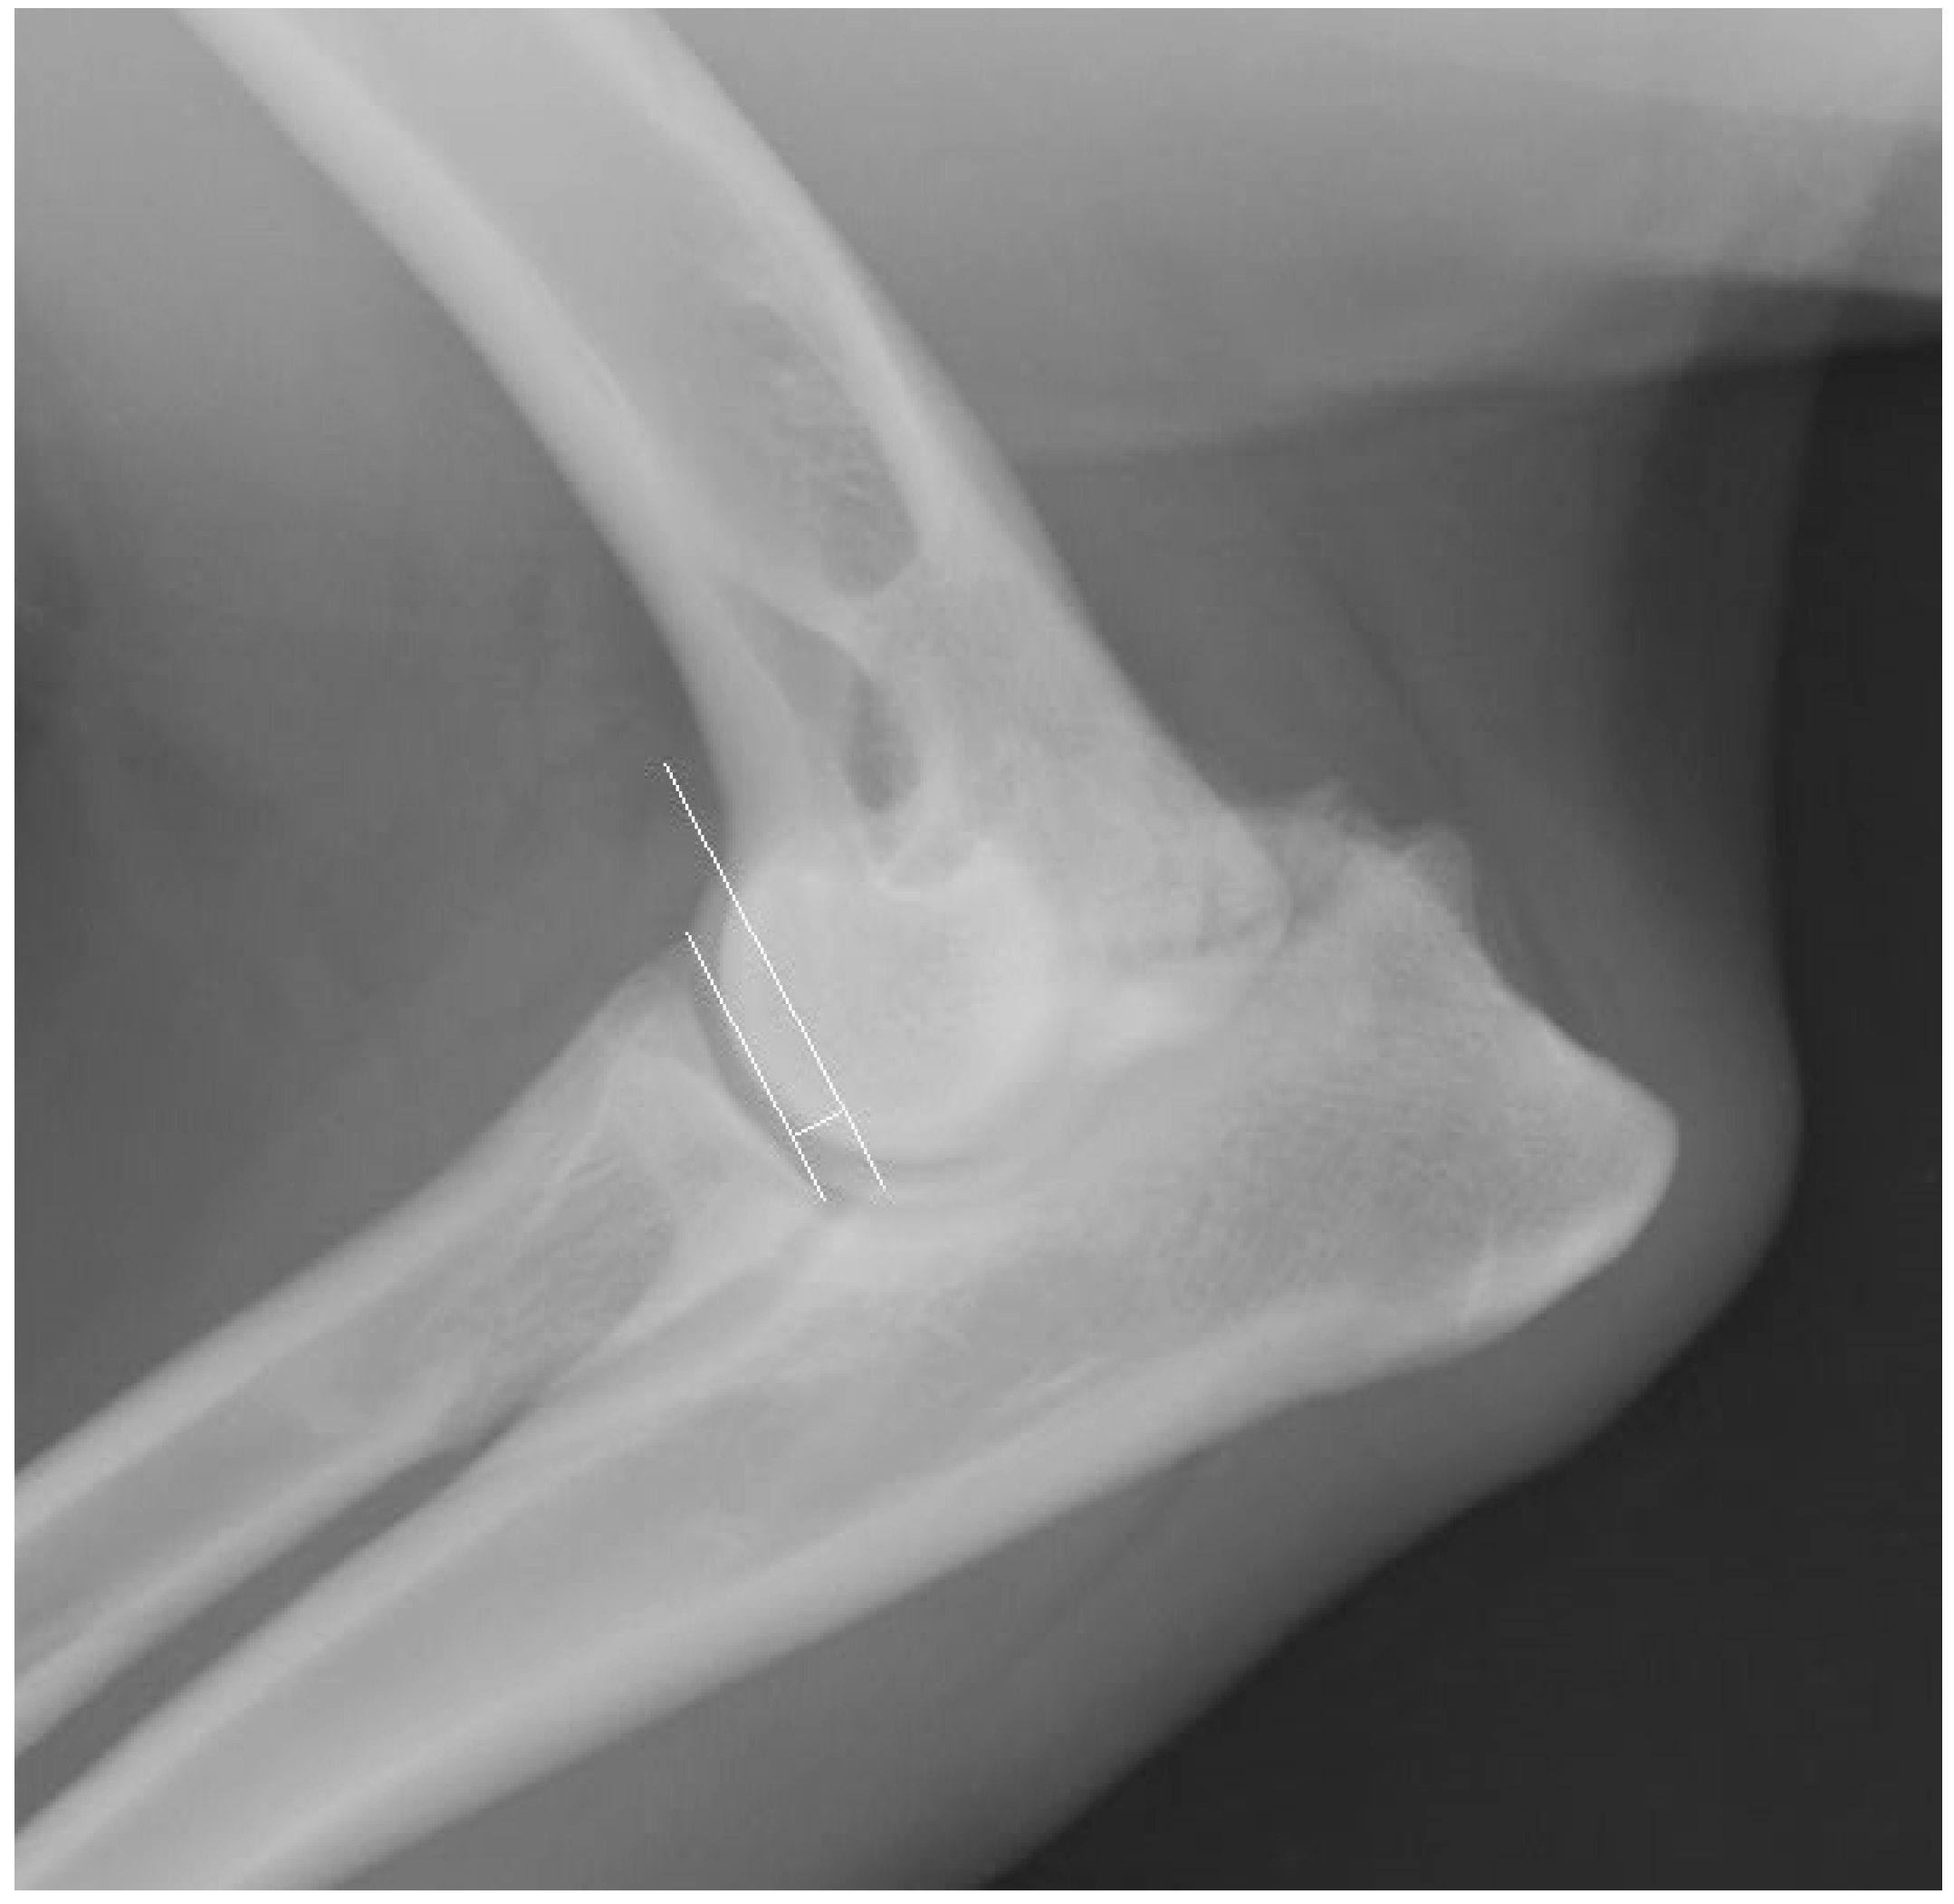

2.3. Radiographic Technique

2.5. Measurement Techniques